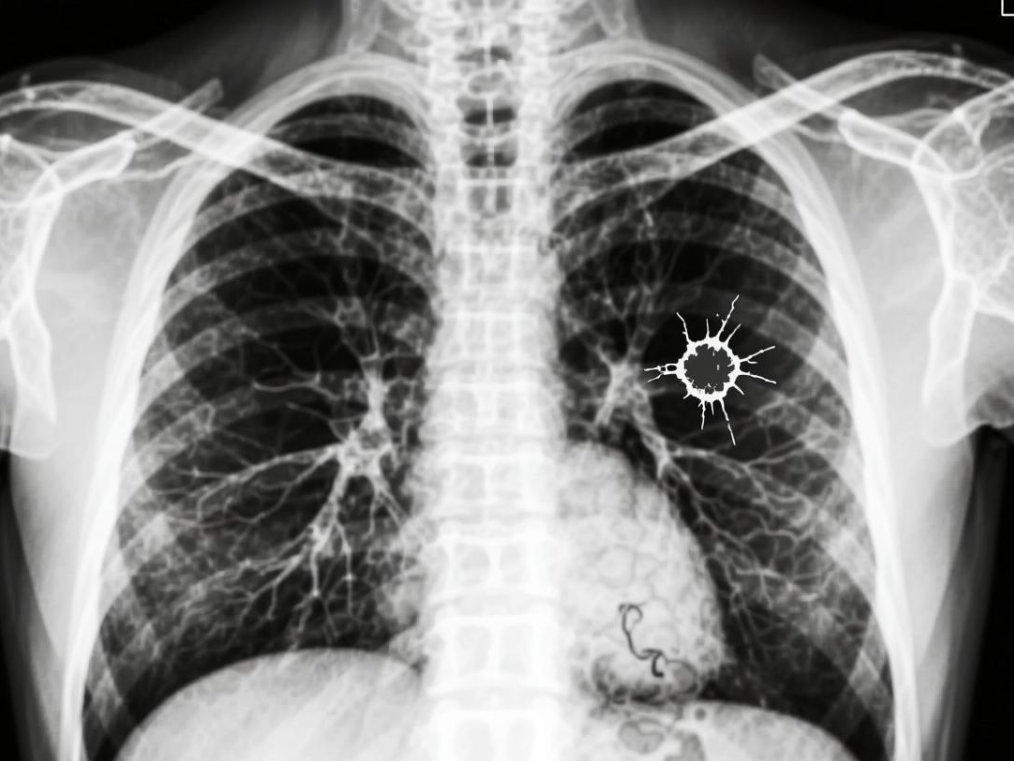

肺鳞癌:起源于肺部支气管黏膜的鳞状上皮细胞,癌细胞形态像“鳞片”一样,多发生在肺部的中央区域(靠近主支气管、肺门),所以也叫"中央型肺癌"。

肺腺癌:起源于肺部支气管黏膜的腺上皮细胞,癌细胞能分泌黏液,多发生在肺部的周围区域(靠近肺的边缘),故而也称之为“周围型肺癌”。

形象点说,肺鳞癌更像长在肺部“主干道”附近的肿瘤,而肺腺癌更像长在肺部“分支小路”末端的肿瘤位置不同,后续的症状和检查发现难度也会不一样。